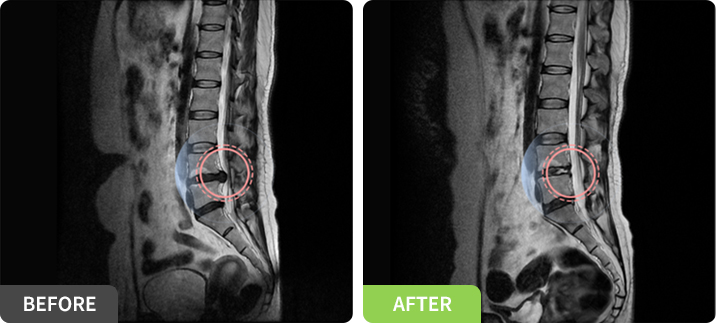

경막외 신경성형술 (PEN)

꼬리뼈 위 쪽 구멍을 통해 특수카테터를 삽입하여 척추신경 주변의 염증과 유착을 제거하는 치료법

요추, 경추의 추간판 탈출증, 척추관 협착증, 척추 수술 후 증후군이 있는 환자들에게 도움이 되는 치료방법입니다.

피부를 절개하지 않고 가느다란 특수 카테터를 꼬리뼈의 경막외강을 통해 척추의 내부로 삽입하여 척추 신경에 생긴 염증 유발 물질 및 유착들을 인위적으로 박리, 제거하고 염증이 재발하지 않도록 특수 처방된 약제를 주입하는 시술입니다.